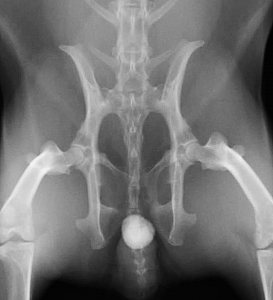

下の写真は膀胱結石が尿道結石となり尿路閉塞を生じた一連の変化をレントゲンで撮影したものです。数週間にわたる血尿と「排尿時のしぶり」と頻回尿を症状とする排尿障害を起こしていたウサギのものです。レントゲン検査では1cm程の膀胱結石が確認されました。

膀胱炎にやそれに伴う頻尿などの諸症状に対する対症療法を行ってもあまり症状の改善がみられないため、手術を計画しましたが、その前に排尿困難に陥って緊急で来院した際のレントゲン写真が下の二枚です。膀胱内にあった結石が尿道結石となり急性の尿路閉塞を生じています。